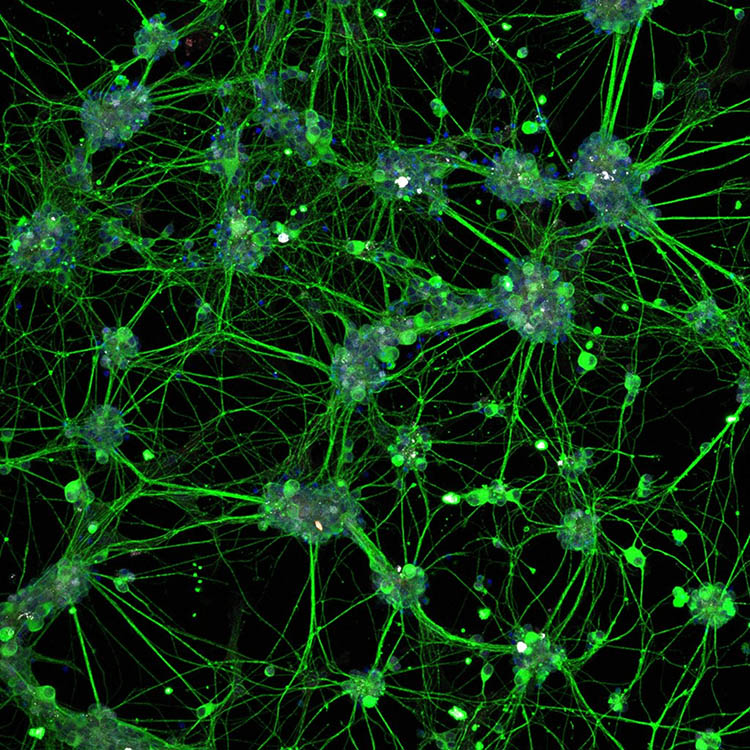

Tissue engineering and regenerative ophthalmology is a field that has been making remarkable strides in recent years, revolutionizing the way we treat eye diseases and injuries. Using cutting-edge technologies and innovative approaches, researchers in this field are developing advanced materials, biocompatible scaffolds, and bioactive molecules that can help restore vision and repair damaged eye tissues. From corneal transplants and retinal implants to stem cell therapies and gene editing, the possibilities in tissue engineering and regenerative ophthalmology are truly awe-inspiring. With its potential to improve the quality of life for millions of people worldwide, it's no wonder that this field is considered one of the coolest and most exciting areas of research today.

Regenerative Cellular Therapies

Stem Cell Derived Retinal Organoids